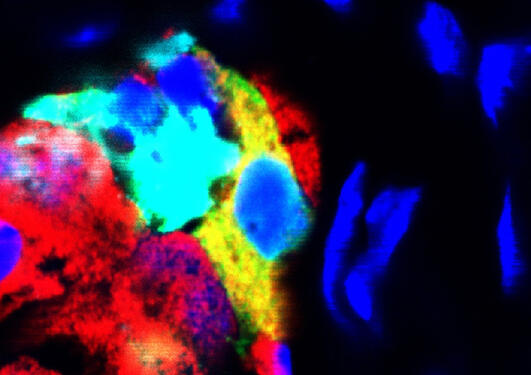

Helge Ræder and his colleagues found that human cells can change their main task.